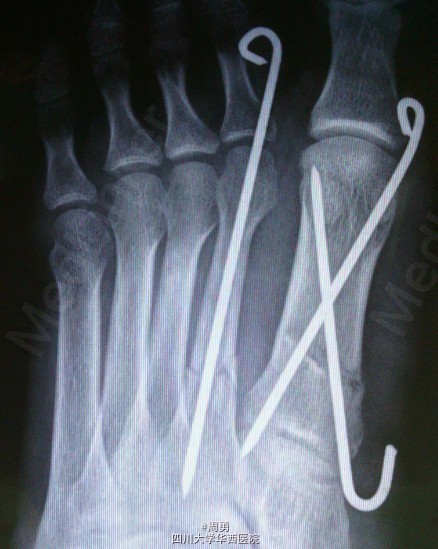

左足第1,2跖骨中近1/3骨折闭合复位克氏针内固定术

此手术为做博士住院总时所做,复位比较满意,价格便宜,效果确实。病例简介:33Y,M,诊断:左足第1,2跖骨中近1/3骨折;处理:行闭合复位克氏针内固定术。